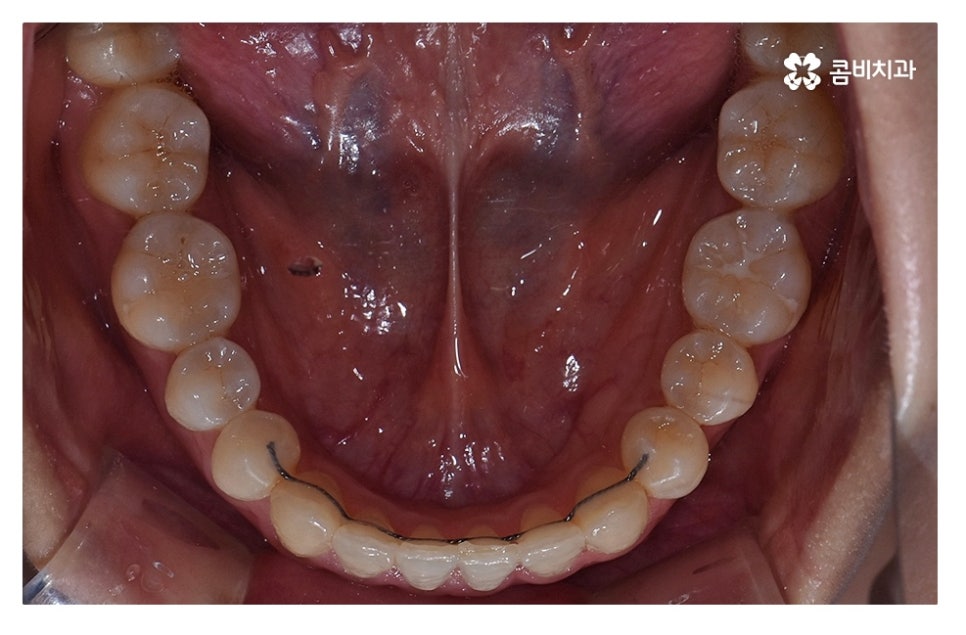

오늘 보여드릴 사례도 덧니교정이 비발치로 진행이 된 사례이며

치아의 이동 공간과 치아 상태, 골격, 얼굴형 등을

종합적으로 판단할 때 비발치로도 진행이 가능했던 사례라고 할 수 있어요.

교정 장치의 선택에 있어서는 다양한 교정 장치의 선택이 가능한데

심미성이 강조된 설측교정부터 콤비교정,

위 환자분의 사례처럼 클리피씨교정이 보편적으로 많이 활용되고 있는데요.

클리피씨교정은 치아의 이동이 일반 장치에 비해 상대적으로

빠르기 때문에 치료 기간이 단축될 수 있으며

통증의 감소, 내원 횟수를 줄일 수 있다는 장점 등이 있어요.